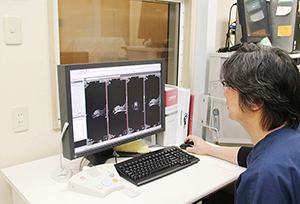

位置決めが容易になったコンソール |

検査では,セッティング後に野口院長が位置決めをして,撮像を開始する。検査中は看護師が管理を行い,野口院長は診察や処置をしながら合間に画像を確認している。撮像時間は平均で40分ほどだが,検査時間全体は以前と比べて大きく短縮していると野口院長は話す。

「以前は位置決めが難しく撮り直すこともありましたが,現在は非常に楽になりました。また,AIRIS Light では3軸が連動して一度に設定できます。あまり検査時間が延びると患者さんの負担となるため,後日に再検査を行うこともありましたが,更新後は検査時間が短縮し,患者さんや飼い主さんに負担を掛けずにすんでいます」

診断では,必要に応じて過去画像との比較も行っている。2016年2月にはPACSを導入し,フィルム運用からデジタルへと移行した。検査の結果は,診察室でモニタを使って説明しており,フィルムよりも理解しやすいと飼い主からも好評だ。